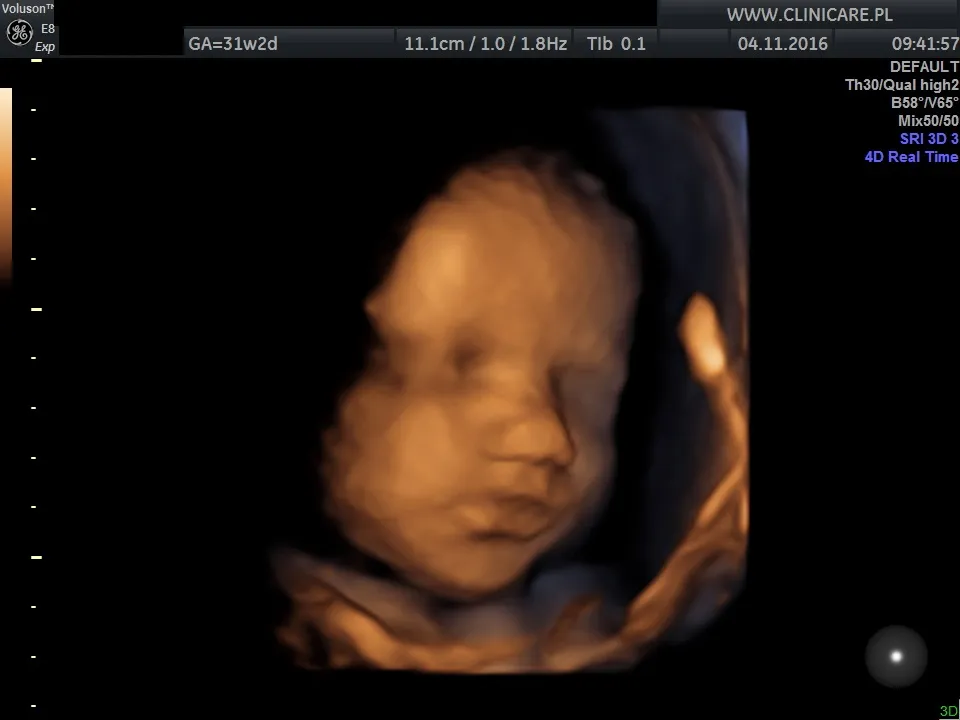

Jednym z najważniejszych badań w tym okresie jest USG III trymestru, które zazwyczaj wykonuje się między 28. a 32. tygodniem ciąży. Podczas tego badania lekarz oceni wiele kluczowych parametrów. Sprawdzi wzrost i ułożenie płodu, co jest ważne w kontekście zbliżającego się porodu. Oceniona zostanie również ilość wód płodowych, która świadczy o prawidłowym funkcjonowaniu nerek dziecka i ogólnym dobrostanie. Ponadto, lekarz dokładnie skontroluje położenie łożyska, aby upewnić się, że nie ma żadnych przeciwwskazań do porodu drogami natury.